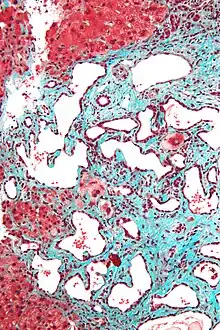

Histopathology of a bile duct hamartoma, high magnification, H&E stain. It shows typical features of bile duct hamartoma: Small to medium sized, irregularly shaped bile ducts lined by bland cuboidal epithelium (may also be flattened). Prominent intervening collagenous stroma. Bile ducts containing eosinophilic debris (may also contain inspissated bile)

Micrograph of a bile duct hamartoma. Trichrome stain, high magnification